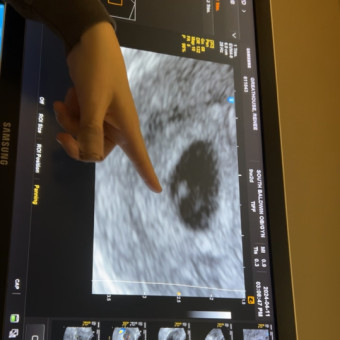

Incoming! Baby Craig!

Renee Greathouse & Dylan Craig

Loxley, AL

December 6, 2024

It’s been a long wait, but we can all now celebrate! Baby Craig coming December 2024! ❤️